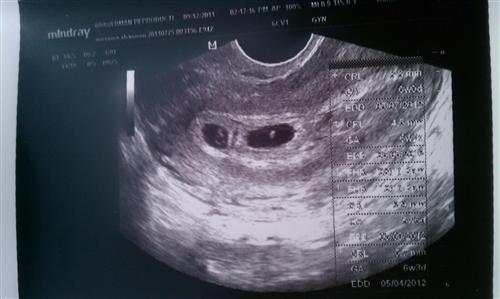

Our Chat Icon Chat Icon BOTH have heartbeats!!!! Chat Icon Chat Icon Chat Icon Chat Icon

Thank you so much for all of your Chat Icon Chat Icon and good wishes to us!!! We go back on Saturday b/c Dr. B still couldn't get measurements on Baby B. Chat Icon I'm thrilled to get to see them again so soon, but am still nervous... Chat Icon

ETA: Forgot to add that we got to HEAR baby A's heartbeat today too. Chat Icon Chat Icon

Baby B is further back he said Chat Icon and he can't get a great visual yet but we could SEE the heartbeat, but we couldn't hear it yet... hopefully Saturday we'll be able to. Chat Icon Chat Icon

Image Attachment(s):